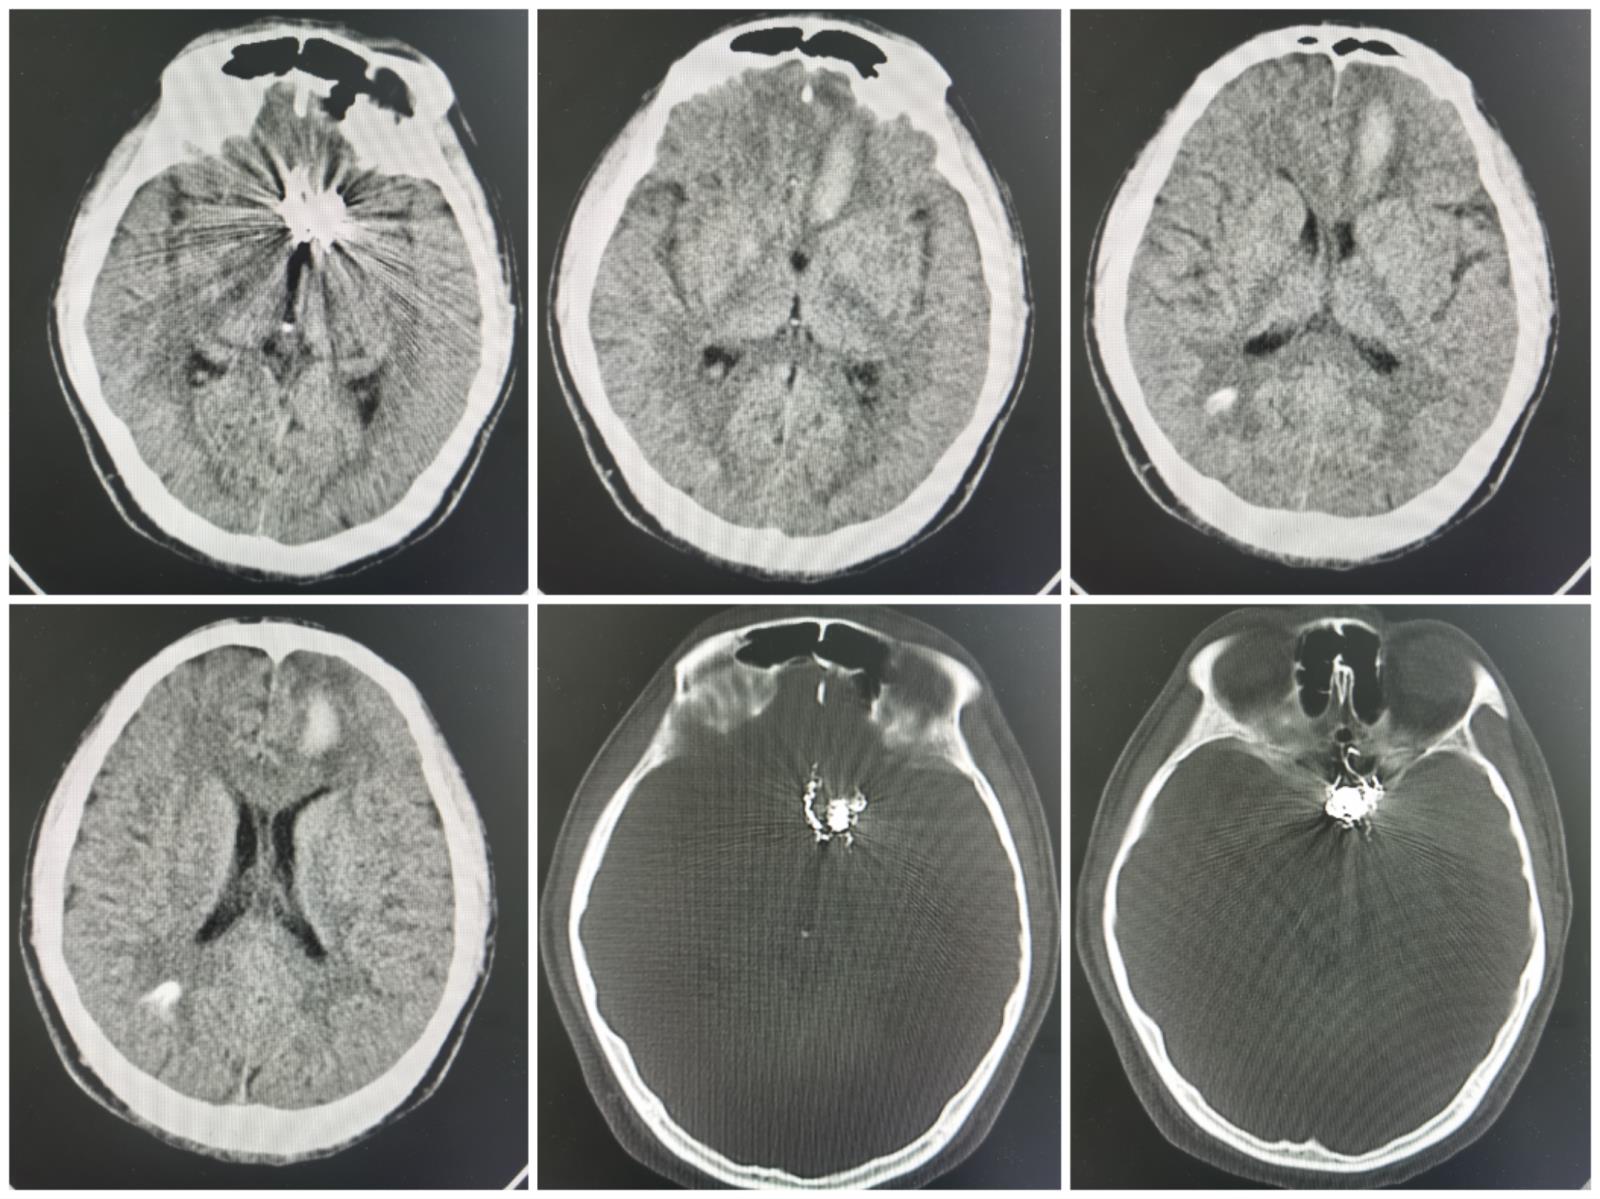

术后影像